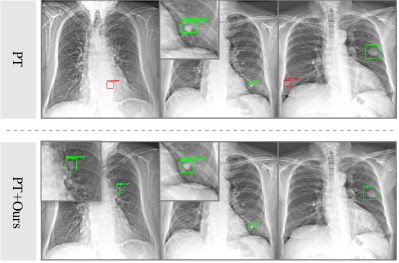

Qualitative Comparison. In a visual demonstration, we provide evidence of the superiority of our proposed method. In Fig. 3, we present the performance of PT and our method in domain adaptive lung nodule detection from CXR to NODE21. As illustrated in Fig. 3, our model effectively mitigates false positives. Furthermore, our method demonstrates superior performance in true positive detection, achieving both higher confidence scores and more accurate localization.

Refer to caption

Figure 3: The comparison of the detection results of lung nodules between the approaches and our method in the scenario of CXR to NODE21. The small image serves as a magnified view of a specific region. The red boxes and green boxes denote the false positives (FP) and true positives (TP).